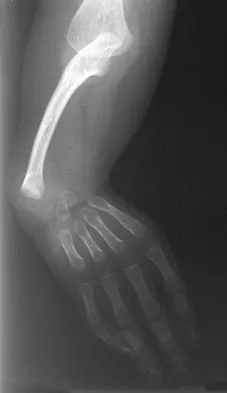

Figure 31 shows the AP and lateral radiographs of the elbow of a 56-year-old man with chronic polyarticular rheumatoid arthritis. His function continues to be limited by pain with activities of daily living. Examination shows that his total arc of motion is 110 degrees. Nonsurgical management has failed to provide relief. Treatment should now consist of

A semiconstrained prosthesis can provide excellent results in carefully selected patients. Because the radiographs show extensive joint destruction with loss of the capitellum and trochlea, a capitellocondylar total elbow (unconstrained) prosthesis is contraindicated. Elbow fusion is poorly accepted, and the radiographs show too much articular destruction for a radial head excision, synovectomy, or interposition arthroplasty to be effective. Ewald FC, Simmons ED Jr, Sullivan JA, et al: Capitellocondylar total elbow replacement in rheumatoid arthritis: Long-term results. J Bone Joint Surg Am 1993;75:498-507.